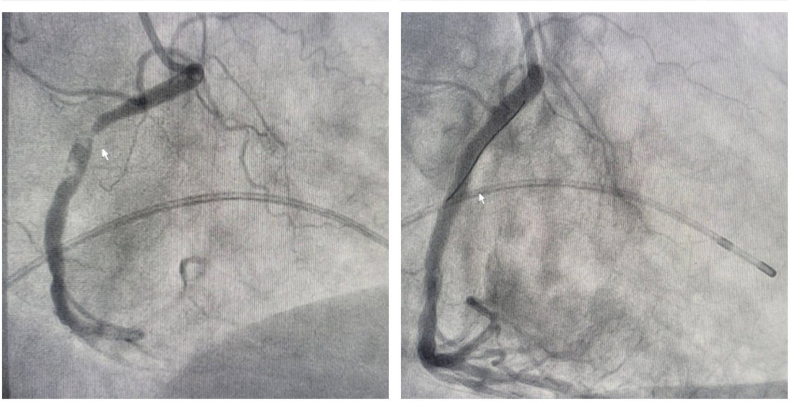

Hình ảnh các nhánh mạch vành tắc trước can thiệp (trái) và được tái lưu thông sau can thiệp (phải)

Kết quả chụp mạch vành bằng hệ thống chụp mạch số hóa xóa nền DSA cho thấy tổn thương tắc hai trong ba nhánh mạch vành – tắc hoàn toàn động mạch liên thất trước, tắc gần hoàn toàn động mạch vành phải, có nhiều huyết khối. Ekip can thiệp do Ths.BS Đinh Danh Trình đã thực hiện kỹ thuật can thiệp hút huyết khối, đặt 2 stent vào động mạch liên thất trước và động mạch vành phải để nong tổn thương hẹp, tạo hình mạch vành, tái thông dòng chảy cho mạch vành tưới máu cơ tim cải thiện. Ngay sau can thiệp, bệnh nhân thoát nguy kịch, được điều trị hồi sức tích cực, không còn đau tức ngực, huyết động ổn định.